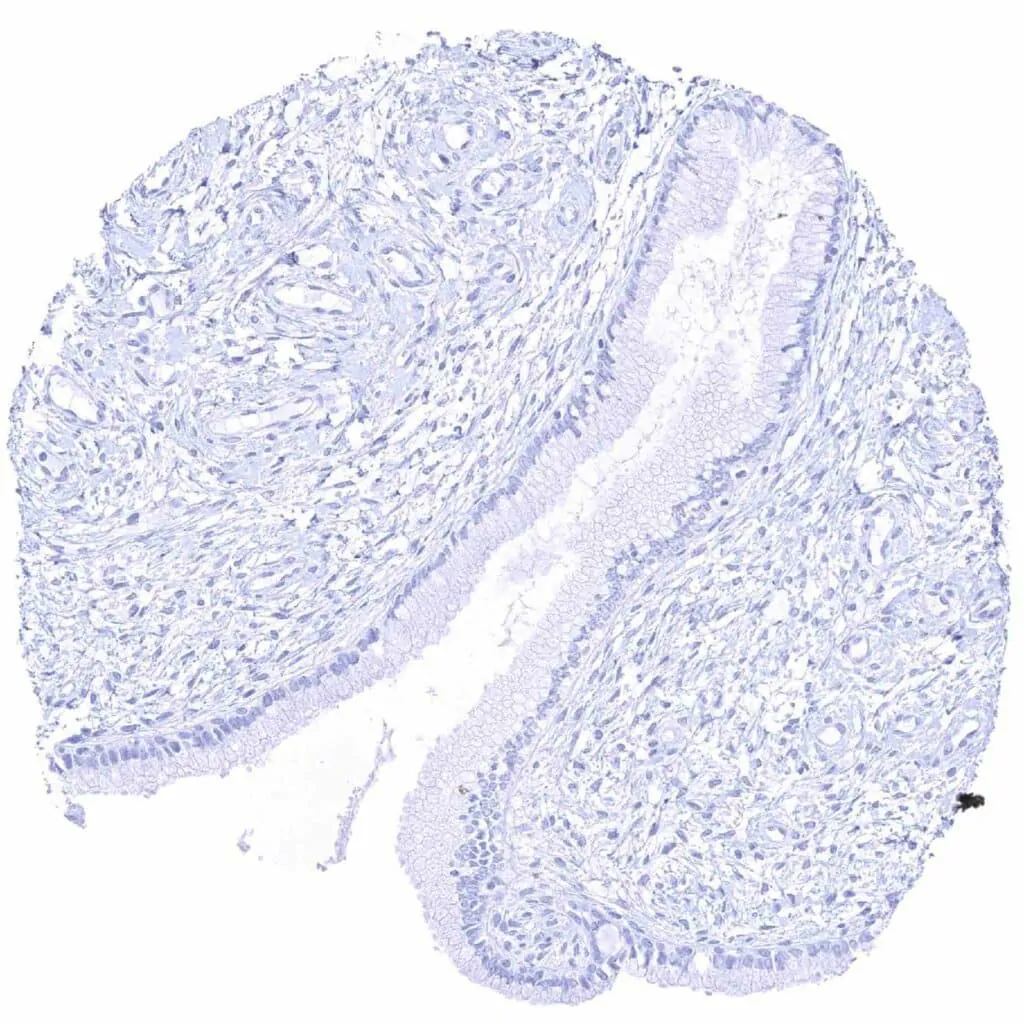

Uterus, endocervix